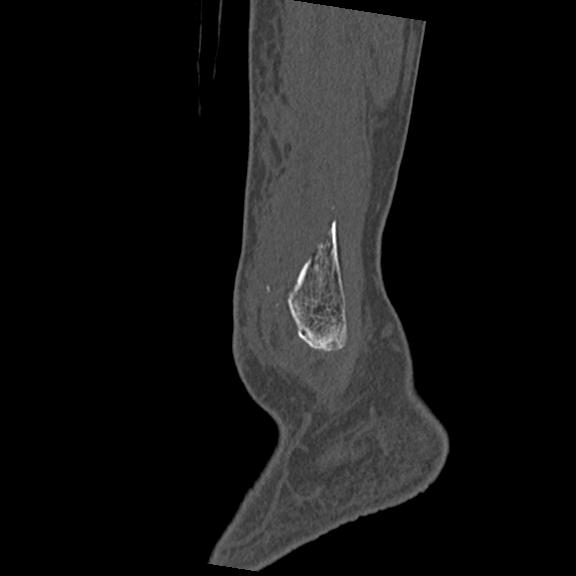

56476 8/28 4R 1/21 2R 左足関節 デジカメ写真 72歳女性 右足関節AS